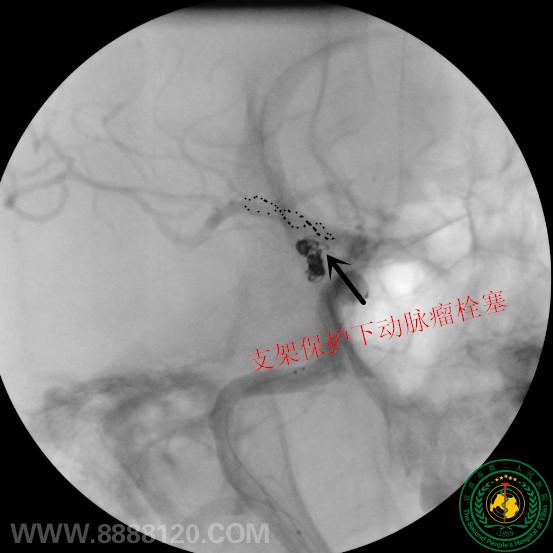

我科采用Lvis支架半释放技术完成复杂后交通动脉瘤介入治疗

我科采用Lvis支架半释放技术完成复杂后交通动脉瘤介入治疗9679